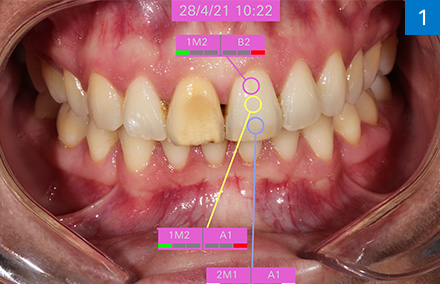

Taïwan : Cas VITABLOCS du Dr Mon Li et de la prothésiste dentaire Sally Hsieh

Dr. Mon Li et Prothésiste dentaire Sally Hsieh, CEREC Asie, Taipei, Taïwan

« Le dégradé de couleurs intégré en quatre couches d’intensité permet un jeu de couleurs et de lumière naturel dans la zone esthétique. »

Une histoire à succès : Reconstitution vivante de dents antérieures en céramique feldspathique polychrome

Situation initiale

Après un traitement radiculaire, une patiente de 20 ans n’était pas satisfaite de la coloration foncée de la 11, qui ne présentait par ailleurs aucun symptôme. La radiographie a montré une obturation radiculaire suffisante.

Solution

Après consultation approfondie, la patiente a choisi une restauration rapide par couronne en tout céramique à base de céramique feldspathique polychrome VITABLOCS TriLuxe forte afin de stabiliser la 11 à long terme et de répondre à ses attentes esthétiques. La morphologie originale devait être conservée et a donc été scannée avant la préparation pour la conception de la couronne. La détermination précise de la couleur de la dent adjacente a été réalisée avec le VITA Easyshade V afin de pouvoir choisir le bloc adéquat.

Pourquoi VITABLOCS TriLuxe forte ?

Nous avons utilisé VITABLOCS TriLuxe forte car la patiente souhaitait une restauration coronaire hautement esthétique et définitive en une seule séance dans la zone esthétique. Grâce au dégradé de couleur intégré et au brillant jeu de couleurs et de lumière du bloc de céramique feldspathique polychrome, nous avons pu obtenir le résultat souhaité avec un minimum de caractérisations, malgré le petit corridor temporel.

Le spectrophotomètre VITA Easyshade V a permis de déterminer avec précision la couleur de la dent.

La couleur de dent 2M1 déterminée numériquement a été documentée à l’aide de la barrette de couleur échantillon correspondante.

La morphologie initiale a pu être reprise pour la conception de la couronne.

Le positionnement de la restauration dans le bloc permet de contrôler le dégradé de couleur.

La couronne terminée sur le modèle après une caractérisation minimale avec VITA AKZENT Plus.

Le résultat hautement esthétique obtenu avec la céramique feldspathique VITABLOCS TriLuxe forte.